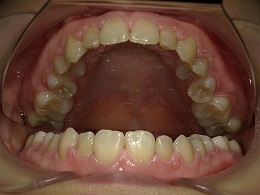

治療前上顎

治療中上顎

治療後上顎

お試し矯正後、深い噛み合わせ改善のため上下全体矯正中の患者様の症例になります。